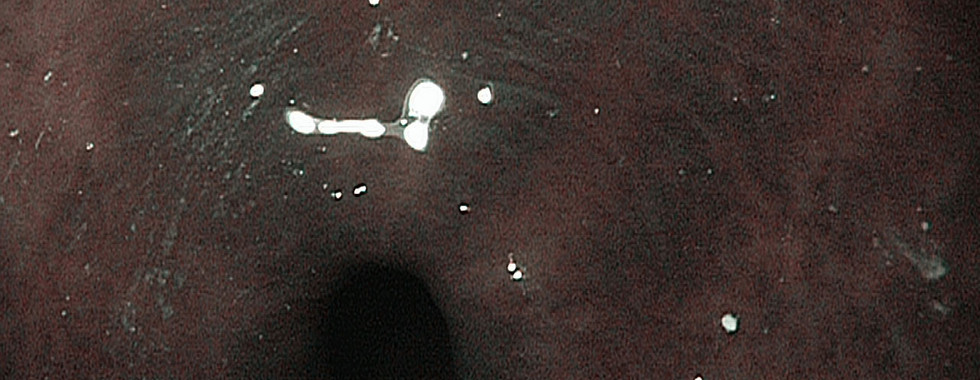

Gastric intestinal metaplasia often does not cause noticeable symptoms, making it difficult to detect without proper screening. Usually, gastric intestinal metaplasia is detected during gastroscopy most noticeable when the doctor uses Narrow Band Imaging (NBI) to screen for these precancerous lesions during gastroscopy.